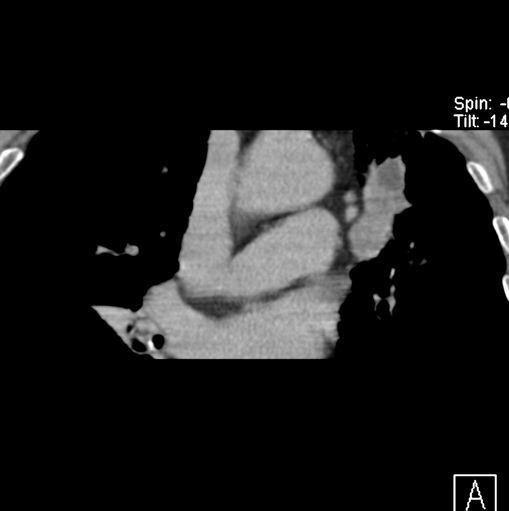

标题: CT25434:胸部CT增强扫描

男性患者 81岁 咳嗽 咳痰 咯血

肿块贴近左肺门,包绕左上肺动脉,形态不规则。肿块增强扫描中度强化。纵膈内主动脉弓左旁间隙、气管隆突前、下间隙见多枚淋巴结影。综上考虑左侧中央型肺癌可能性大。图片没有完整上传,尤其是左肺上叶支气管分支层面没有上传,因此不好判断是叶支气管中断还是段支气管中断。另外,下图红色部分所示是“黏液支气管征”吗?